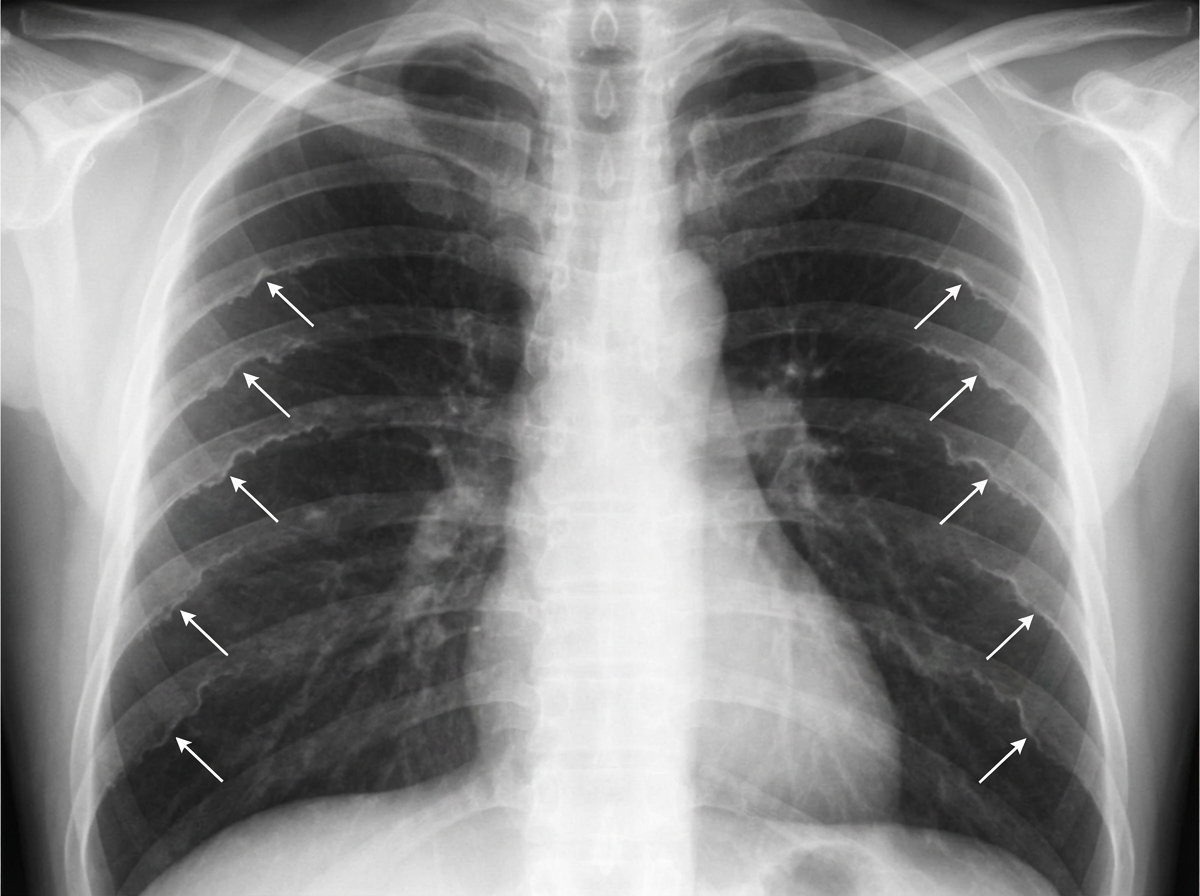

The sign marked by the arrows pointing to the ribs, in the provided chest X-ray, is diagnostic of which of the following conditions?

Explanation: ### Explanation **Correct Answer: C. Coarctation of the aorta** The clinical presentation of hypertension in a young male, left ventricular hypertrophy (LVH), and specific rib changes is classic for **Coarctation of the Aorta**. In this condition, there is a narrowing of the aorta (usually distal to the left subclavian artery). To bypass the obstruction, extensive collateral circulation develops via the internal mammary and intercostal arteries. The **dilated, tortuous intercostal arteries** erode the lower margins of the ribs, leading to the characteristic **"Rib Notching" (Roesler’s Sign)**. * **Key Detail:** Notching typically involves the **3rd to 8th ribs**. It is seen on the **inferior/posterior** aspect (though the question mentions "anterior ends," in standard radiology, it is the inferior-posterior aspect of the ribs that is classically notched). * **Radiological Sign:** The "Figure of 3" sign on X-ray (pre-stenotic and post-stenotic dilatation) and the "E-sign" on barium swallow. **Why other options are incorrect:** * **A. Pheochromocytoma:** While it causes hypertension and headache, it does not produce collateral circulation or rib notching. * **B. Carcinoid syndrome:** Presents with flushing, diarrhea, and right-sided heart failure; it has no association with rib notching or aortic narrowing. * **D. Superior mediastinal syndrome:** Usually caused by a mass obstructing the SVC. While it may show dilated neck veins, it does not cause lower-body hypertension or the specific rib notching pattern seen in coarctation. **High-Yield Clinical Pearls for NEET-PG:** * **Rib Notching (Inferior):** Coarctation of aorta, Blalock-Taussig shunt, or subclavian artery stenosis. * **Rib Notching (Superior):** Hyperparathyroidism, Polio, or Osteogenesis Imperfecta. * **Radio-femoral delay:** The hallmark physical exam finding in Coarctation. * **Turner Syndrome:** Frequently associated with Coarctation of the Aorta (approx. 15-20% of cases).

Explanation: ***Coarctation of aorta*** - **Rib notching** (Roesler's sign) occurs due to **dilated intercostal arteries** that serve as collateral circulation, eroding the **inferior margins of ribs 3-8**. - This classic radiological finding develops as intercostal arteries enlarge to bypass the **aortic narrowing**, creating characteristic scalloping of the rib undersurfaces. *Hyperthyroidism* - Causes **osteoporosis** and **generalized bone demineralization**, not specific rib notching or erosion patterns. - Chest X-ray may show **cardiomegaly** or **enlarged thyroid**, but intercostal artery dilatation does not occur. *Chronic renal failure* - Results in **renal osteodystrophy** with **rugger jersey spine**, **brown tumors**, and **looser zones**, not rib notching. - Bone changes are metabolic in nature due to **hyperparathyroidism** and **vitamin D deficiency**, not vascular collateralization. *Multiple myeloma* - Produces **punched-out lytic lesions** and **pathological fractures** throughout the skeleton, including ribs. - Creates **discrete round lesions** rather than the smooth **inferior rib erosions** characteristic of vascular notching.